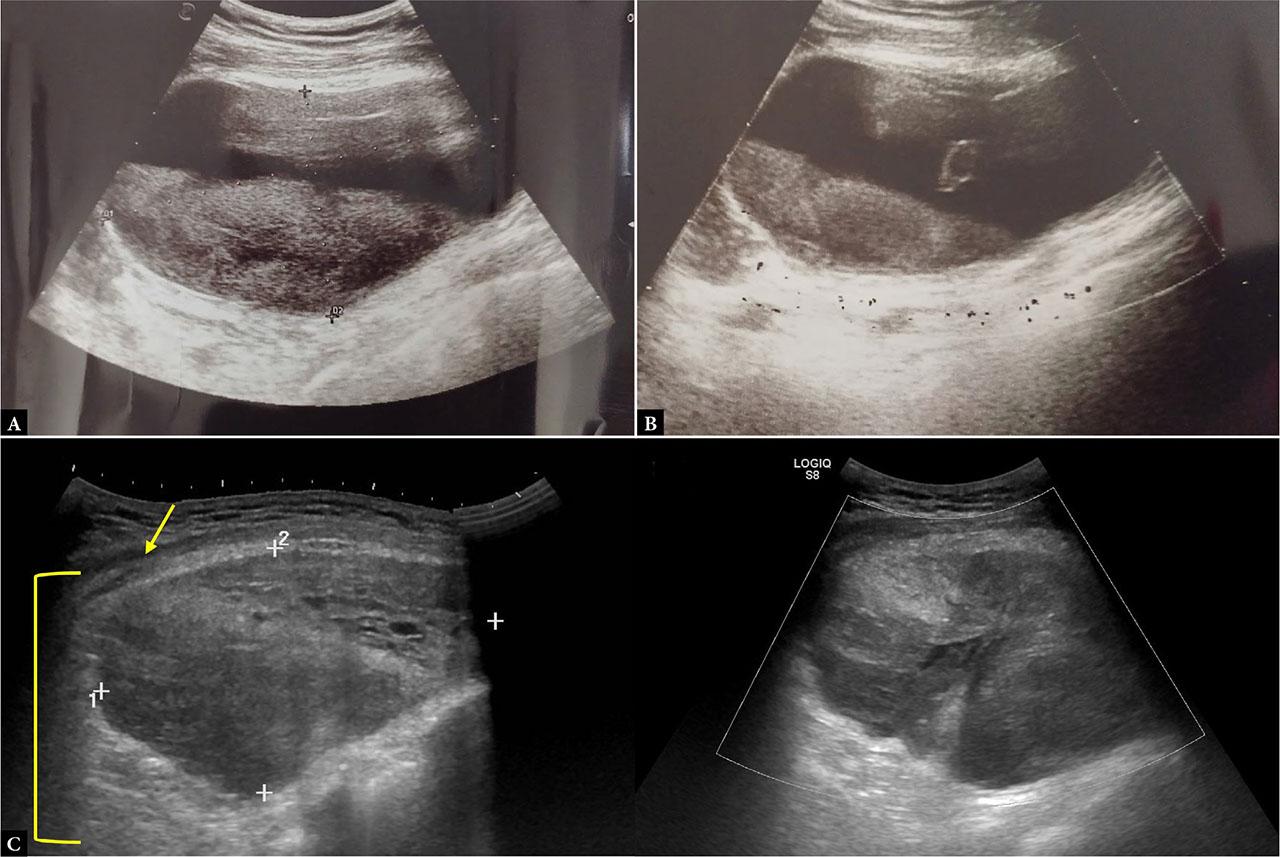

An initial bedside US of the chest wall was performed to investigate the etiology of the swelling. The findings were highly suggestive of a subacute hematoma, based on the clinical timeline (approximately one week after onset) and characteristic sonographic features, including internal echogenic sediment, fine septations, and a fluid–fluid level, with no detectable internal vascularity on CD. However, since an evolving infectious component could not be excluded, clinical and laboratory monitoring was advised, along with follow-up imaging. A repeat US examination performed a few days later demonstrated evolution of the known lesion: the collection was now more disorganized in appearance, consistent with clot lysis and organization, and had increased in size. These findings were compatible with a hematoma in evolution (Fig. 2). In this case, the increased size of the lesion and the patient’s altered hemoglobin level were the determining factors for proceeding with contrast-enhanced CT to exclude active contrast medium spread.

Ultrasound of the right pectoral region showing a large heterogeneous subfascial (yellow arrow) intramuscular (yellow bracket) collection (12 × 6 × 12 cm) without internal vascularity on CD, consistent with a subacute iatrogenic hematoma (A, B, C). Follow-up US performed one week later (D) demonstrates increased disorganization, internal echogenic strands, and persistent absence of vascular signal, confirming hematoma evolution

Educational tip: Use a convex probe for deep or bulky lesions. In subacute or organized hematomas, echogenic sediment and internal lysis may be observed. Always compare lesions over time for evolution. The lesion’s location beneath the fascial plane helps differentiate it from superficial collections such as seromas.

Clinical correlation: The temporal link with catheter removal and progressive swelling makes an iatrogenic hematoma the most plausible diagnosis. Anticoagulation status (not specified but crucial) would further increase the bleeding risk.